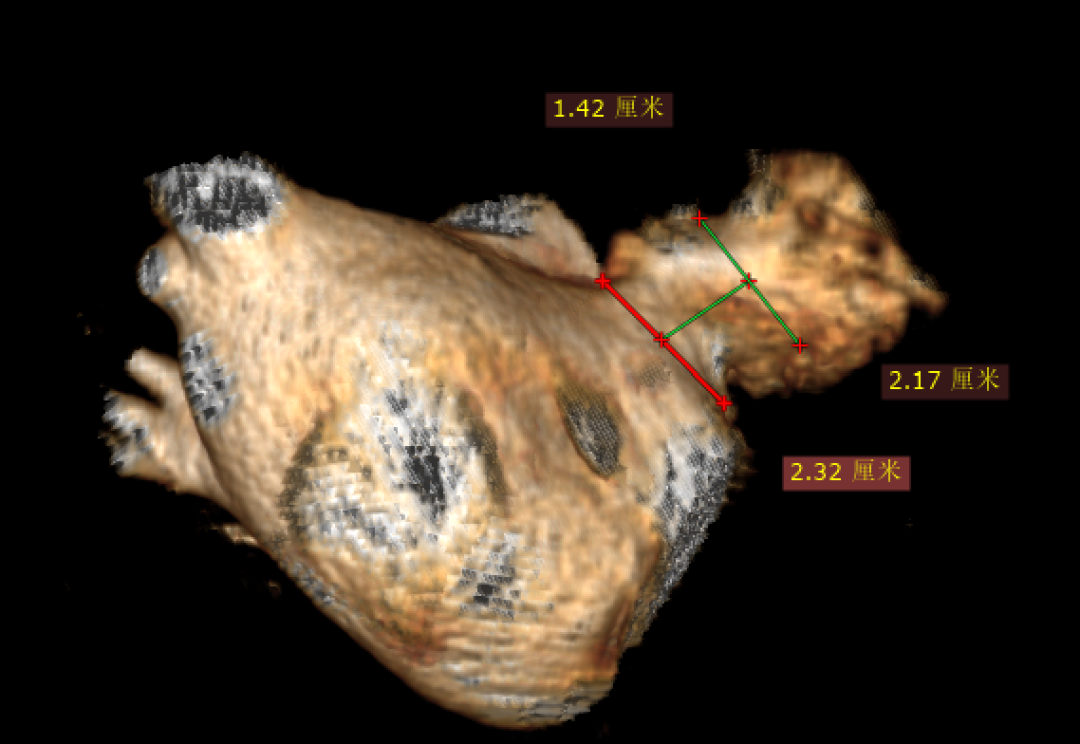

左心房CTA- 多平面测量&3D:锚定区:18.2-21.7mm,开口区:21.8mm*24.2mm。